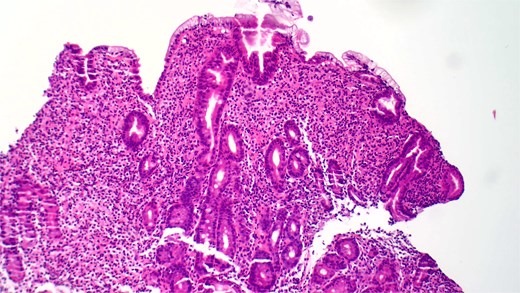

She underwent an EGD, which demonstrated mild chronic duodenitis and erythematous gastric mucosa. Biopsies were obtained from the gastric body, antrum, and duodenum. Histopathological examination revealed abnormal mast cell proliferation in the duodenum (Fig. 1), confirmed by positive staining for CD117 and tryptase, with aberrant CD25 expression (Fig. 2). The gastric mucosa exhibited focal intestinal metaplasia, though no dysplasia was noted. Molecular analysis identified C-KIT D816V mutation. Given these findings, serum tryptase levels were obtained, and additional hematologic evaluation was recommended to assess systemic involvement. The patient was referred to hematology for further assessment of potential bone marrow involvement and systemic treatment options.

Hematoxylin and eosin (H&E) staining reveals abnormal proliferation of mast cells.